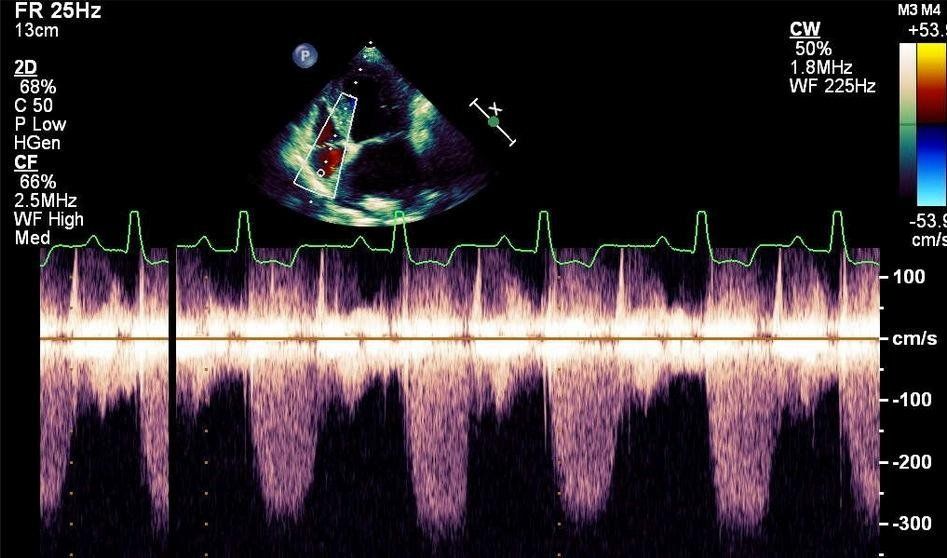

cardiologia veterinaria a vicenza

Medicina cardiovascolare è pratica specialistica della medicina interna che coinvolge il cuore, i vasi sanguigni e spesso il sistema respiratorio.

Malattie cardiache sono comuni negli animali da compagnia, e spesso possono essere trattate con successo o addirittura guarite.

Cardiologi veterinari usano la loro preparazione specialistica, una serie di test diagnostici e apparecchiature di immagine per arrivare alla diagnosi.

Indagine del apparato cardiocircolatorio inizia con un esame fisico con particolare attenzione sui fattori che indicano la funzione cardiaca, come il colore delle mucose orali, tempo di riempimento capillare, frequenza cardiaca a riposo, ritmo cardiaco, auscultazione cardiaca e polmonare, la frequenza respiratoria a riposo.

La malattia di cuore può essere primaria o secondaria ad altre condizioni come l'ipertensione, malattie della tiroide, disturbi elettrolitici, malattie infettive, malattie respiratorie e cancro. Cronica insufficienza mitralica valvolare, cardiomiopatia (DCM, HCM), ipertensione polmonare, dotto arterioso pervio (PDA), stenosi subaortica (SAS), stenosi polmonare (PS), difetto del setto ventricolare (VSD), insufficienza cardiaca congestizia (CHF), tachicardie, bradicardie e versamento pericardico sono alcune delle condizioni che comunemente riscontriamo nel cane e nel gatto.

Nella nostra clinica controllo cardiologico avviene alla prima visita clinica del cucciolo, in età di 55 – 60 gg per escludere eventuali cause congenite della malattia cardiaca. Dopo l’età di 7 anni nei cani e nei gatti è consigliata la visita cardiologica che consiste in esame fisico, controllo dell’attività elettrica del cuore (elettrocardiogramma – ECG), esame radiografico e esame tomografico-ecocardiografico (esame più valido nello studio delle valvole cardiache).